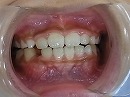

治療前 治療後

治療後の写真では、咬合バランスが改善しています。

今後、永久歯の矯正によって、美しい歯並びに改善していく予定です。